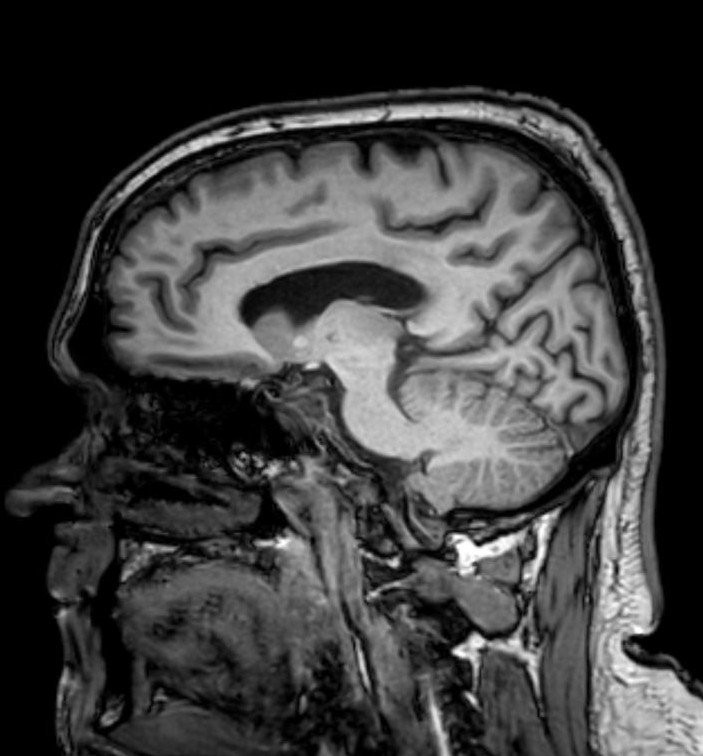

V nemocnici následne absolvoval CT. Lekári sa najprv domnievali, že ide o krvácanie spôsobené nárazom, no podrobnejšie vyšetrenia odhalili niečo vážnejšie. Jamieho následne poslali do Sheffieldu, kde chirurg identifikoval mozgový nádor vyžadujúci urgentnú operáciu. Podstúpil kraniotómiu, pri ktorej odstránili všetok viditeľný nádor, no po zákroku sa musel znovu učiť chodiť aj rozprávať.